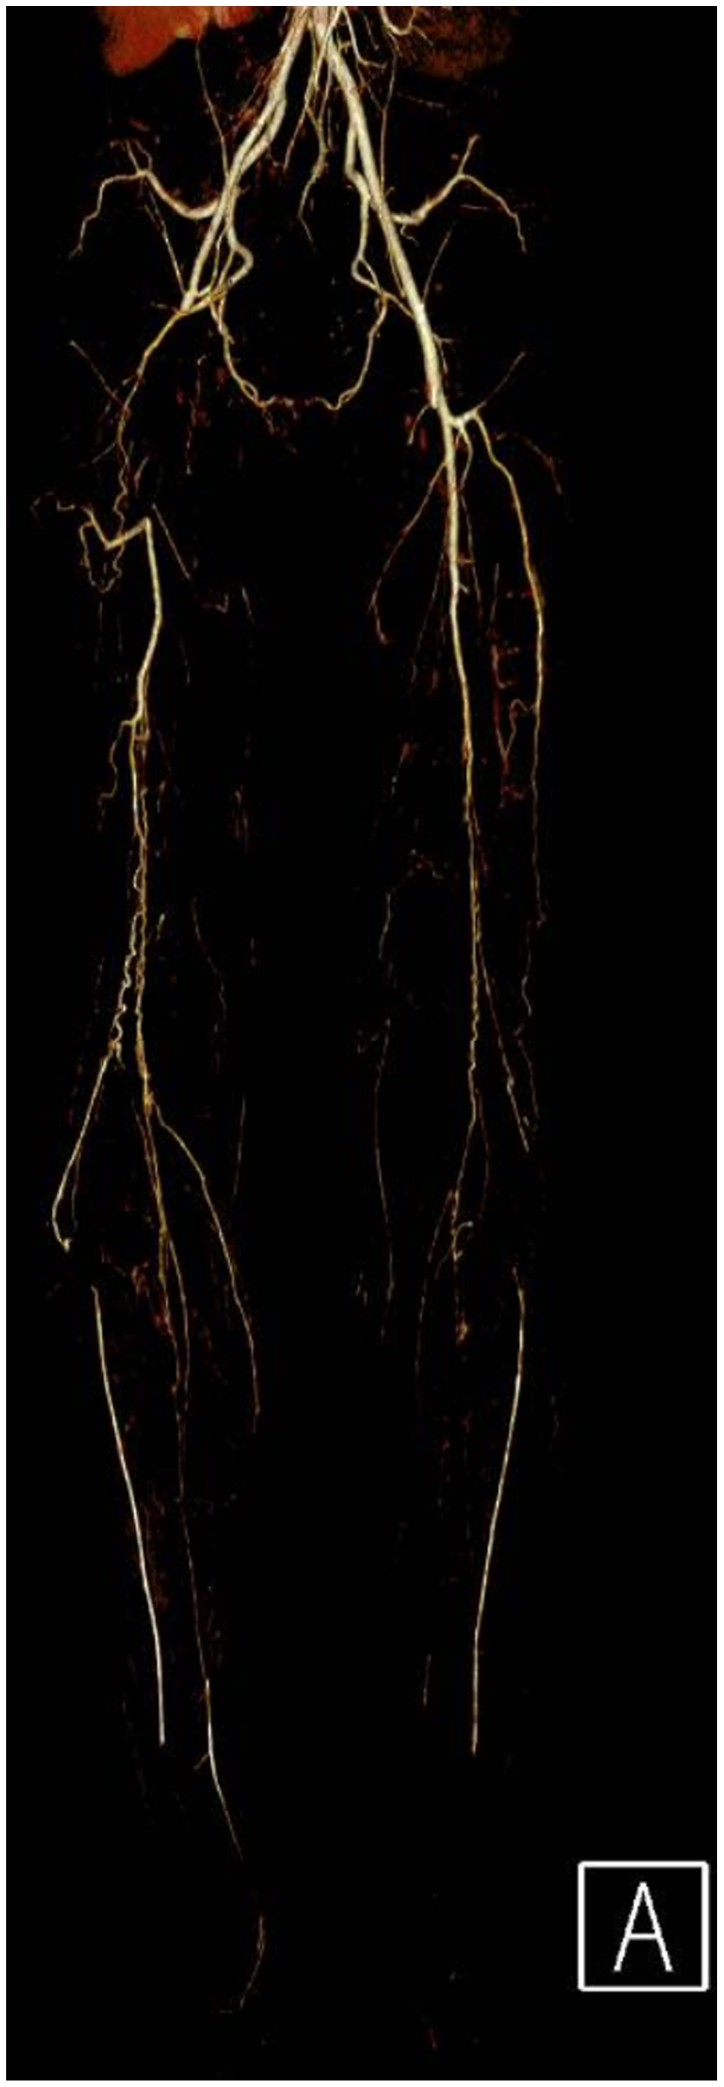

Clinical examination revealed non-palpable dorsalis pedis and posterior tibial pulses bilaterally. The lower extremities were warm, without sensory or motor deficits or evidence of tissue loss. Vascular studies demonstrated an ankle-brachial index of 0.36 on the right and 0.45 on the left. Subsequent workup including a computed tomographic angiography, and arterial duplex imaging revealed occlusion of the right common femoral and distal right superficial femoral arteries with reconstitution of tibial vessels. (Figs 1 and 2). The left lower extremity demonstrated a similar pattern of disease without the common femoral artery occlusion. Extensive workup of other possible etiologies for peripheral vascular disease, including hereditary thrombophilias and other vasculitic syndromes, was negative. Labs were notable for normal immunologic and inflammatory markers, a hemoglobin A1C of 5.7, and a normal lipid panel.

It is unclear if cannabis arteritis represents a subtype of TAO or a distinct clinical entity due to the predominance of concurrent tobacco and cannabis use in as many as 97% of cases reported in the literature.ref. bib2 Furthermore, many recorded substance use histories lack the detail necessary to identify other contributing sources of tobacco exposure, such as the cured tobacco leaves used in blunt wraps.ref. bib4 This case represents a rare instance in which there is minimal exposure to tobacco in both smoking history and “cross-contamination” of cannabis. This patient presented with extensive proximal lesions to the common and superficial femoral arteries and claudication without ischemic ulcerations, which is quite unusual for TAO and may better characterize the unique features of cannabis arteritis.ref. bib6,ref. bib11 To the authors’ knowledge, this also appears to be one of the first case reports linking THC vaping to cannabis arteritis.